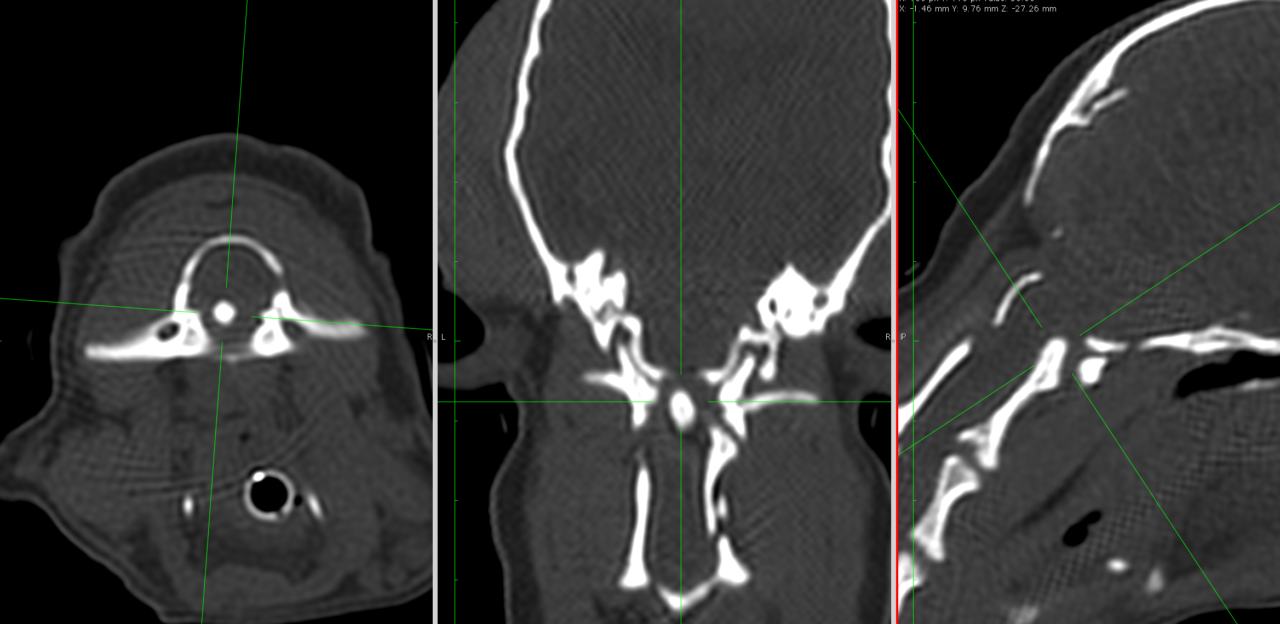

かかりつけの先生から、3歳のチワワが悲鳴をあげて、首を痛がり、歩けなくなっているので、すぐにMRIを撮って原因を調べて必要があれば手術をして欲しいと連絡がありました。すぐに来院され、神経学的な検査とCT・MRIを実施したところ、環椎と軸椎の不安定症が原因とわかりました。すぐに頸部にコルセットを着用し、状態を安定化しました。翌日には小康状態を得ていたので、環軸固定術を行いました。

手術は1.5mmのチタンスクリューを第2頚椎に挿入し、亜脱臼している軸椎を腹側に牽引します。その後、関節面を超音波骨メスにより軟骨を掻爬し、骨面を露出、上腕骨より海綿骨を採取し、関節面に移植します。その後、経関節にポジティブチタンピンを2本、環椎に2本刺入します。

これらをチタンメッシュによりインプラントを一括セルフロック状態とさせます。さらにごく少量の骨セメントでインプラントを固定します。

このチタンメッシュの役割として、セメントの重合熱から骨のオーバーヒートから守る。感染のリスクのあるセメントの消費量を少なくする。関節固定の強度を担保する。また、ステンレスを使わない理由としては、金属アーチファクトが少ないので、術後にMRIの撮影が可能。ステンレスより熱伝導率が悪いため、セメントの重合熱を骨に伝えにくいといったメリットがあると考えています。